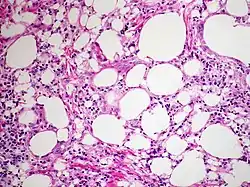

Appearance

The gross appearance of a lipid pneumonia is that in which there is an ill-defined, pale yellow area on the lung. This yellow appearance explains the colloquial term "golden" pneumonia.[7]

At the microscopic scale foamy macrophages and giant cells are seen in the airways, and the inflammatory response is visible in the parenchyma.